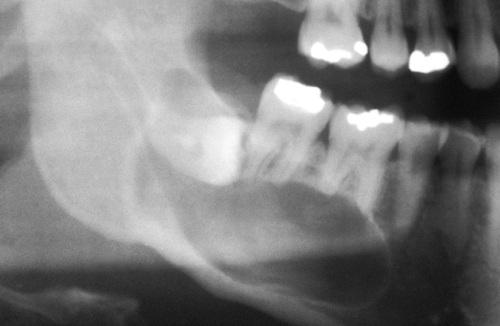

Radiographic Features

- unilocular radiolucent area

- associated with the crown of an unerupted tooth

- well-defined, often corticated border (unless infected)

- root resorption of adjacent erupted teeth can occur

- radiolucent space should be at least 3 to 4 mm in diameter

dentigerous cyst

A unilocular radiolucent cyst involving the crown of an unerupted tooth, with the crown projecting into the cystic cavity.

dentigerous cyst, central type

A unilocular radiolucent cyst along the mesial root of the unerupted molar. This cyst exhibited mucous cell prosoplasia.

dentigerous cyst, lateral type

A unilocular radiolucent cyst extending along the mesial and distal roots of the unerupted tooth.

dentigerous cyst, circumferential type